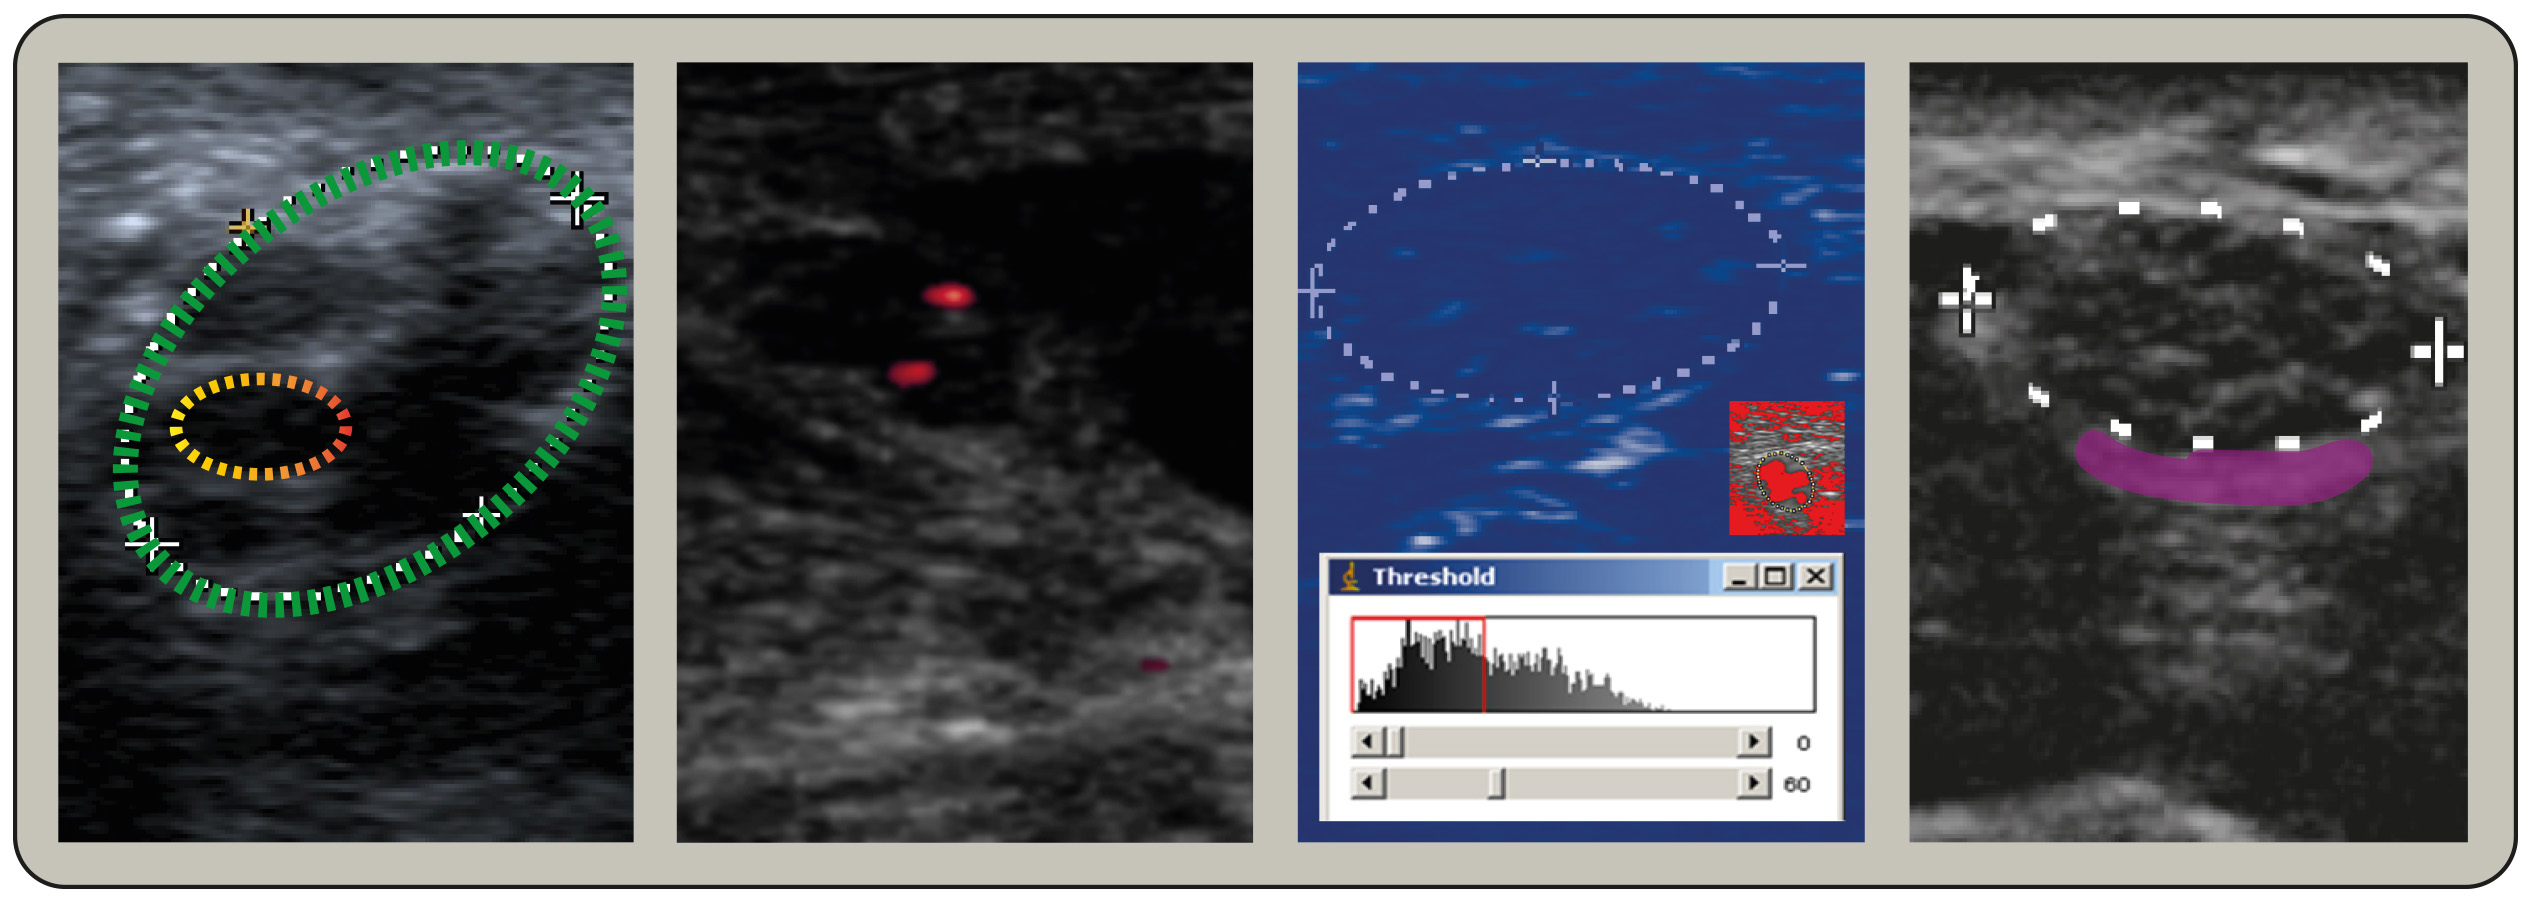

Op een echo kan een tumor er anders uitzien dan een cyste. Vaak heeft hij een onregelmatige vorm, vastere structuur en soms ook bloedvaten eromheen. Maar eerlijk is eerlijk, op een echo is het niet altijd 100% zeker te zeggen of iets goedaardig of kwaadaardig is.

De Echo: Een eerste indruk

De echo is dus een belangrijk hulpmiddel om een eerste indruk te krijgen van wat er zich in je lichaam afspeelt. Het kan een cyste of een tumor opsporen, maar het kan niet altijd met zekerheid zeggen wat het precies is. Zie het als een selfie die je maakt: je ziet jezelf, maar je innerlijk kun je er niet mee vangen.

Het is belangrijk om te beseffen dat een echo vaak slechts het begin is van een onderzoekstraject. Soms is er meer onderzoek nodig, zoals een CT-scan, MRI-scan of biopsie, om een definitieve diagnose te stellen.